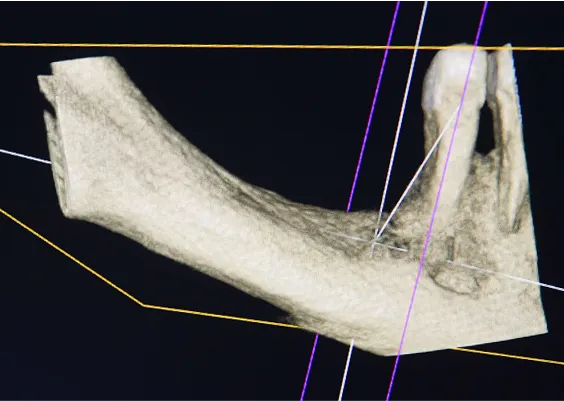

TRÓJWYMIAROWA REKONSTRUKCJA WYROSTKA ZĘBODOŁOWEGO PRZY UŻYCIU INDYWIDUALNIE DRUKOWANYCH SIATEK TYTANOWYCH YXOSS ReOss

To kolejna metoda umożliwiająca precyzyjną odbudowę zadanego kształtu tkanki kostnej przy użyciu standardowych materiałów kościotwórczych, kości własnej lub PRF oraz zewnętrznego rusztowania w postaci siatki z biozgodnego stopu tytanu. Siatka jest indywidualnie projektowana w technologii CAD CAM i następnie drukowana dla konkretnego przypadku.

Dotychczas stosowane stabilizatory zewnętrzne w formie siatek tytanowych używane do regeneracji kostnej lub w zabiegach odtwórczych w chirurgii szczękowo-twarzowej uwzględniały materiały ręcznie doginane i formowane podczas zabiegu operacyjnego. Zastosowanie technologii CAD CAM dla potrzeb druku materiałów przeznaczonych do indywidualnej rekonstrukcji kostnej znacznie poprawiło precyzję i jakość uzyskiwanych efektów. Wdrożenie biozgodnych stopów tytanu do druku siatek zdecydowanie ograniczyło odsetek powikłań zapalnych.

Precyzja projektu druku siatki bazuje na dokładności odwzorowania kształtu kości w stożkowej tomografii komputerowej CBCT, co zapewnia ich dobre przyleganie do podłoża kostnego oraz ogranicza powstawanie powikłań w postaci obnażania się siatek. Precyzja projektu oraz materiał, z którego wykonana jest siatka (biozgodny stop tytanu), powodują, że obnażenie się siatki nie zaburza procesu gojenia i regeneracji kostnej.

Wymaga jedynie większej ilości kontroli pozabiegowych oraz wzmaga czujność higieniczną zarówno ze strony lekarza, jak i pacjenta. Ten rodzaj odbudowy kostnej stosowany jest w sytuacjach złożonych, trójwymiarowych 3D ubytków kości, przy których standardowe metody odbudowy są niewystarczające. Ilość kości, którą możemy uzyskać, stosując tę metodę, to nawet kilka centymetrów sześciennych.

Metoda rekonstrukcji kostnej w oparciu o indywidualnie drukowane siatki z tytanu dla implantacji wszczepów śródkostnych stosowana jest najczęściej jako dwuetapowa. W pierwszym etapie odbudowywana jest kość, natomiast implanty wszczepiane są po okresie 4–6 miesięcy. Na wgojenie implantów oczekujemy od 4 do 6 miesięcy w zależności od miejsca ich lokalizacji. Siatka tytanowa po spełnieniu swojej funkcji rusztowania dla odbudowującej się kości jest następnie usuwana w dniu wszczepienia implantu. Jeżeli kość spełnia odpowiednie warunki, istnieje możliwość zastosowania modyfikacji siatki tytanowej, która umożliwia jednoczesne wprowadzenie implantów wraz z odbudową kostną.

Wariant ten skraca czas od pierwszego zabiegu do wykonania gotowych koron protetycznych na wprowadzonych implantach. Opisane schematy procedur regeneracyjnych wykazują znaczną innowacyjność, jeśli chodzi o wykorzystanie technologii cyfrowej w medycynie odtwórczej. Natomiast w codziennej praktyce chirurgicznej poprawiają precyzję, tempo oraz przewidywalność w świadczeniu usług polegających na odbudowie zniszczonych lub zdeformowanych ludzkich tkanek.